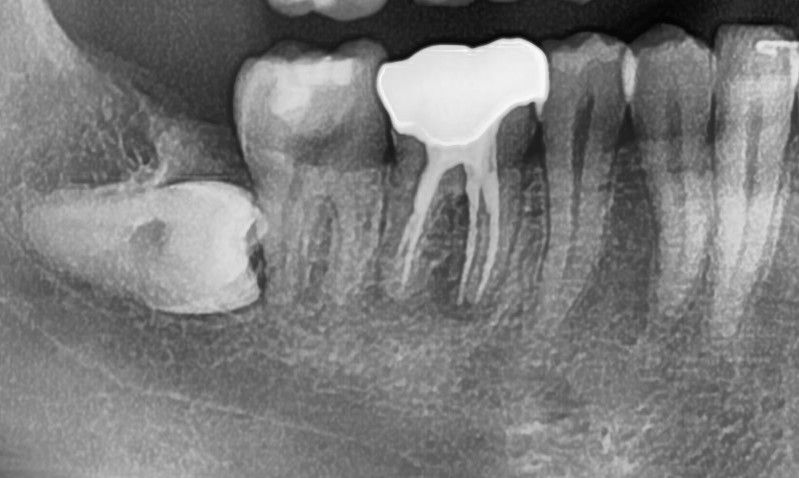

첫번째 사진은 21년도에 찍은 사진이고

두번째 사진은 24년도에 찍은 사진입니다.

두번째 24년도 사진은 파노라마 엑스레이라고 적혀있는데

방사선 사진상으로 볼때 치근단에 염증이 있어 보입니다.

치근단에 염증은 보통 신경관 내부에 감염이 생겼을 때 생기게 됩니다 이런 경우에 따라서는 재신경치료가 필요할 수 있으며 제 신경치료를 하는 경우 보철을 새로 제작해야 할 수 있습니다

1. 전, 후 사진을 비교해봤을 때 뿌리끝 염증이 심해지거나 한 것은 아닌 것 같습니다. 신경치료 이전부터 염증이 잡혀 있었고 그게 커지지도 않고 작아지지도 않은 상태입니다.

2. 다만, 크라운 부위 하방 충치는 의심됩니다.

3. 시리거나 불편한 증상이 있다면 크라운 뜯고 재평가해봐야 하고, 특히 가만히 있을때 아프거나, 씹을때 아프거나 말씀하신 것처럼 농양이 잡혀 나온다면 염증이 문제를 일으키고 있는 것이므로 재신경치료 가능성도 있습니다 .